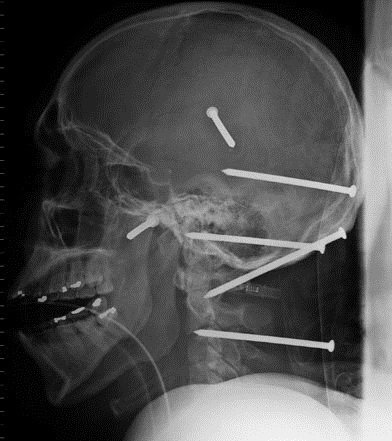

| Radiografía de Israel Mahir, quien sobrevivió tras sufrir un accidente con un martillo eléctrico. |